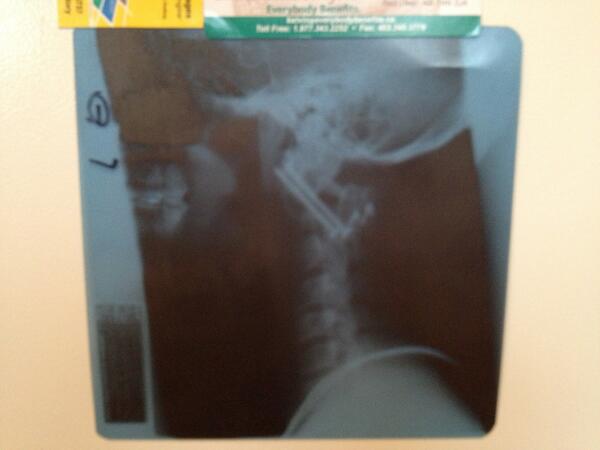

NiteHawks retweetlediTrent Aylward@TheThunder83·26 May@TSNBobMcKenzie @DarrenDreger here's my X-ray. Got more metal in there than Slash's record collection!Çevir English01120